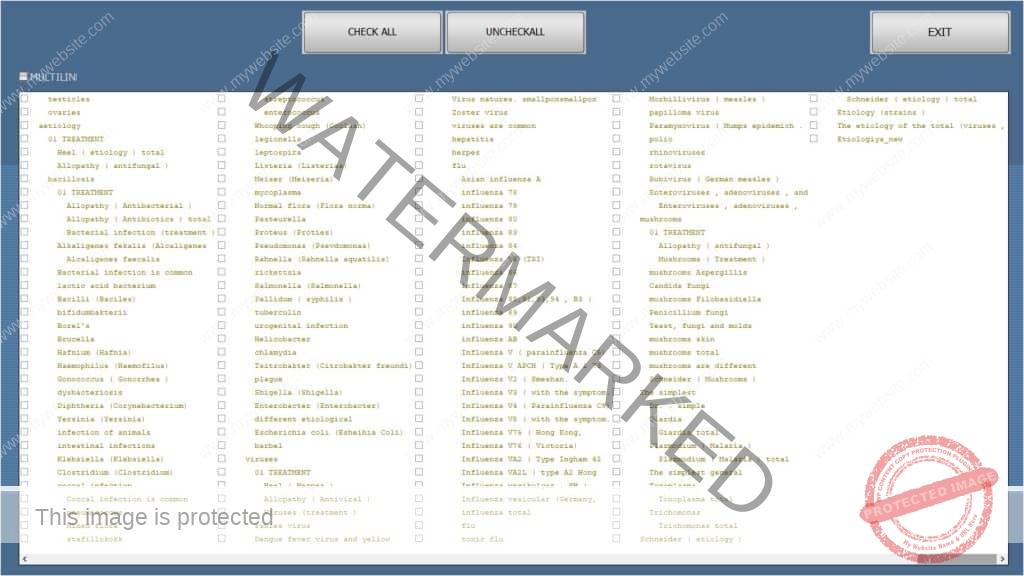

*A preview of the famous ISHA EXPERT SPECIALISTS PACKAGES : THE ISHA VIRUS PRO, THE ISHA DNA PRO, THE ISHA AURA PRO

ISHA Virus Expert Pro, with special in 1 minut to select, GROUP 24, with the “all the important dis ease” making bugs, instead of searching for months/years …. and not knowing. And being frustrated. Not having the real succes with your health, your family, your clients (worldwide) like the ISHA family group in 167 countries. And you get 100 times more etalons (instead of 15) of many healing modalities and A-brand remedies, while others have only 15+ ? 20 ?